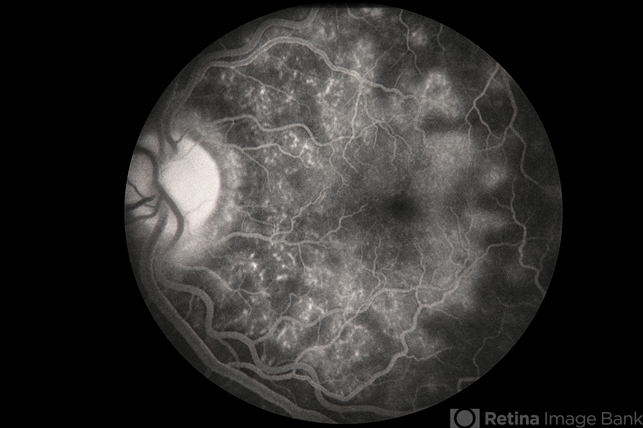

MEWDS

Condition/keywords

multiple evanescent white dot syndrome (MEWDS)

Description

MEWDS.